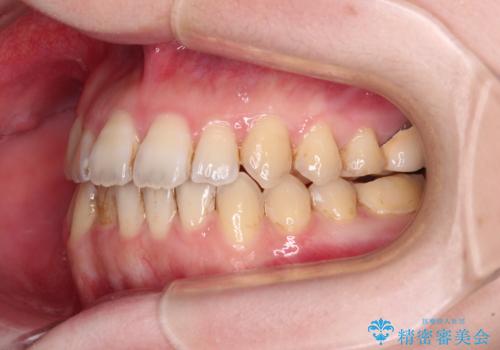

オープンバイトと前歯のデコボコをインビザライン矯正で解消

- 前歯の開咬を気にして来院された患者様です。

開咬の治療は、前歯を閉じるように動かすとともに、上下臼歯を圧下(骨内にめり込ませる)させることで進めて行きます。

インビザラインは臼歯の圧下を効果的に行えるため、インビザラインを用いて矯正治療を行うこととしました。